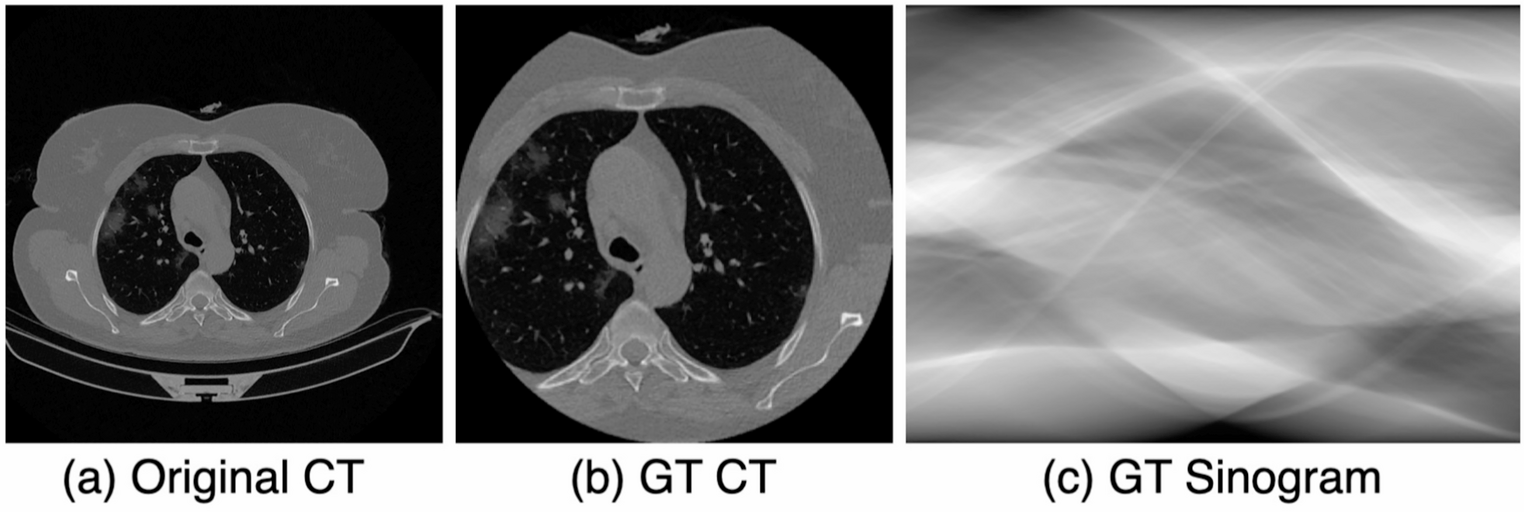

Efficient sparse-view medical image classification for low radiation and rapid COVID-19 diagnosis

This study proposes a deep learning-based diagnostic model called the Projection-wise Masked Autoencoder (ProMAE) for rapi...

Self-supervised learning for CT image denoising and reconstruction: a review

This article reviews the self-supervised learning methods for CT image denoising and reconstruction. Currently, deep learn...